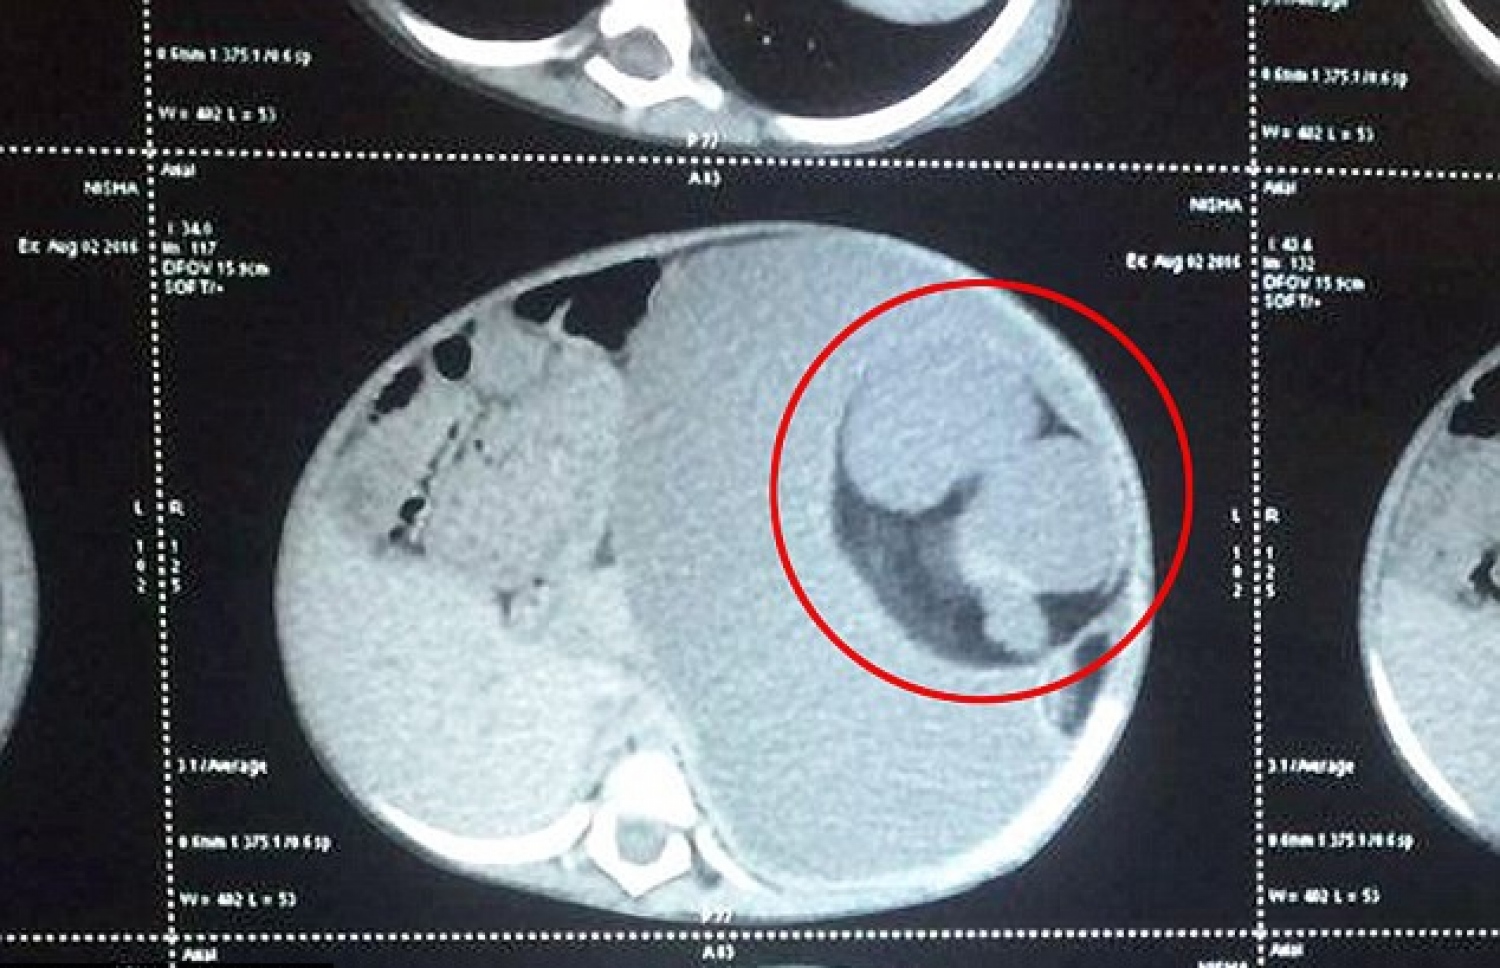

ނިޝާގެ ބަނޑުގެ ސްކޭނުން ބަނޑުގައި އޮތް ކުއްޖާ ފާހަގަކޮށްފައި

ނިޝާ ނަމަކަށް ކިޔާ މި ކުއްޖާގެ ބަނޑު ސްކޭންކޮށް ބެލުމުން އެ ކުއްޖާގެ ބަނޑުން ފެނުނު އެއްޗަކީ ކޮން އެއްޗެއްކަން ޑޮކްޓަރުންނަށް ވެސް ފުރަތަމަ ނޭނގުނެވެ. އެ މީހުންނަށް ޖެހުނީ އޭގެ ހަގީގަތް ހޯދަން އިތުރަށް ދިރާސާތައް ކުރާށެވެ.

އެ ޑޮކްޓަރު ނިޝާ ބަލާފައި އަވަހަށް ބޮޑު ހޮސްޕިޓަލަކަށް ގެންދަން އިރުޝާދު ދިނެވެ. ޑޮކްޓަރުން ފުރަތަމަ ހީކުރީ ނިޝާގެ ބަނޑުގައި އޮތީ ބޮޑު ޓިއުމަރެއް ކަމަށެވެ. ނަމަވެސް ކައްޓާއި ކެލްސިއަމް ޖަމާވެފައިވާ ތަންތަން ހުރިކަން އެނގުމުން އެއީ ޓިއުމަރެއް ނޫންކަމާއި މިއީ ފީޓަސް-އިން-ފެޓޫ ކިޔާ ހާލަތެއްކަން ޔަގީންވި އެވެ.